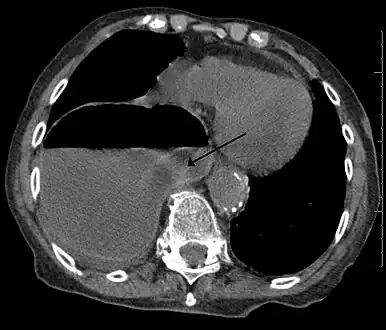

Diaphragmatic hernia is a defect or hole in the diaphragm that allows the abdominal contents to move into the chest cavity. Treatment is usually surgical.

Diagnosis can be made by either CT or X-ray.